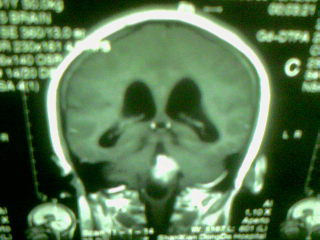

标题: MRI2125:女 45岁 头疼头晕3个月 [打印本页]

标题: MRI2125:女 45岁 头疼头晕3个月

1)考虑第四脑室脉络膜丛乳头状瘤,不排除室管膜瘤。2)阻塞性脑积水。

考虑 第四脑室脑膜瘤或室管膜瘤或脉络膜丛乳头状瘤伴梗阻性脑积水

第四脑室脉络丛乳头状瘤,典型!